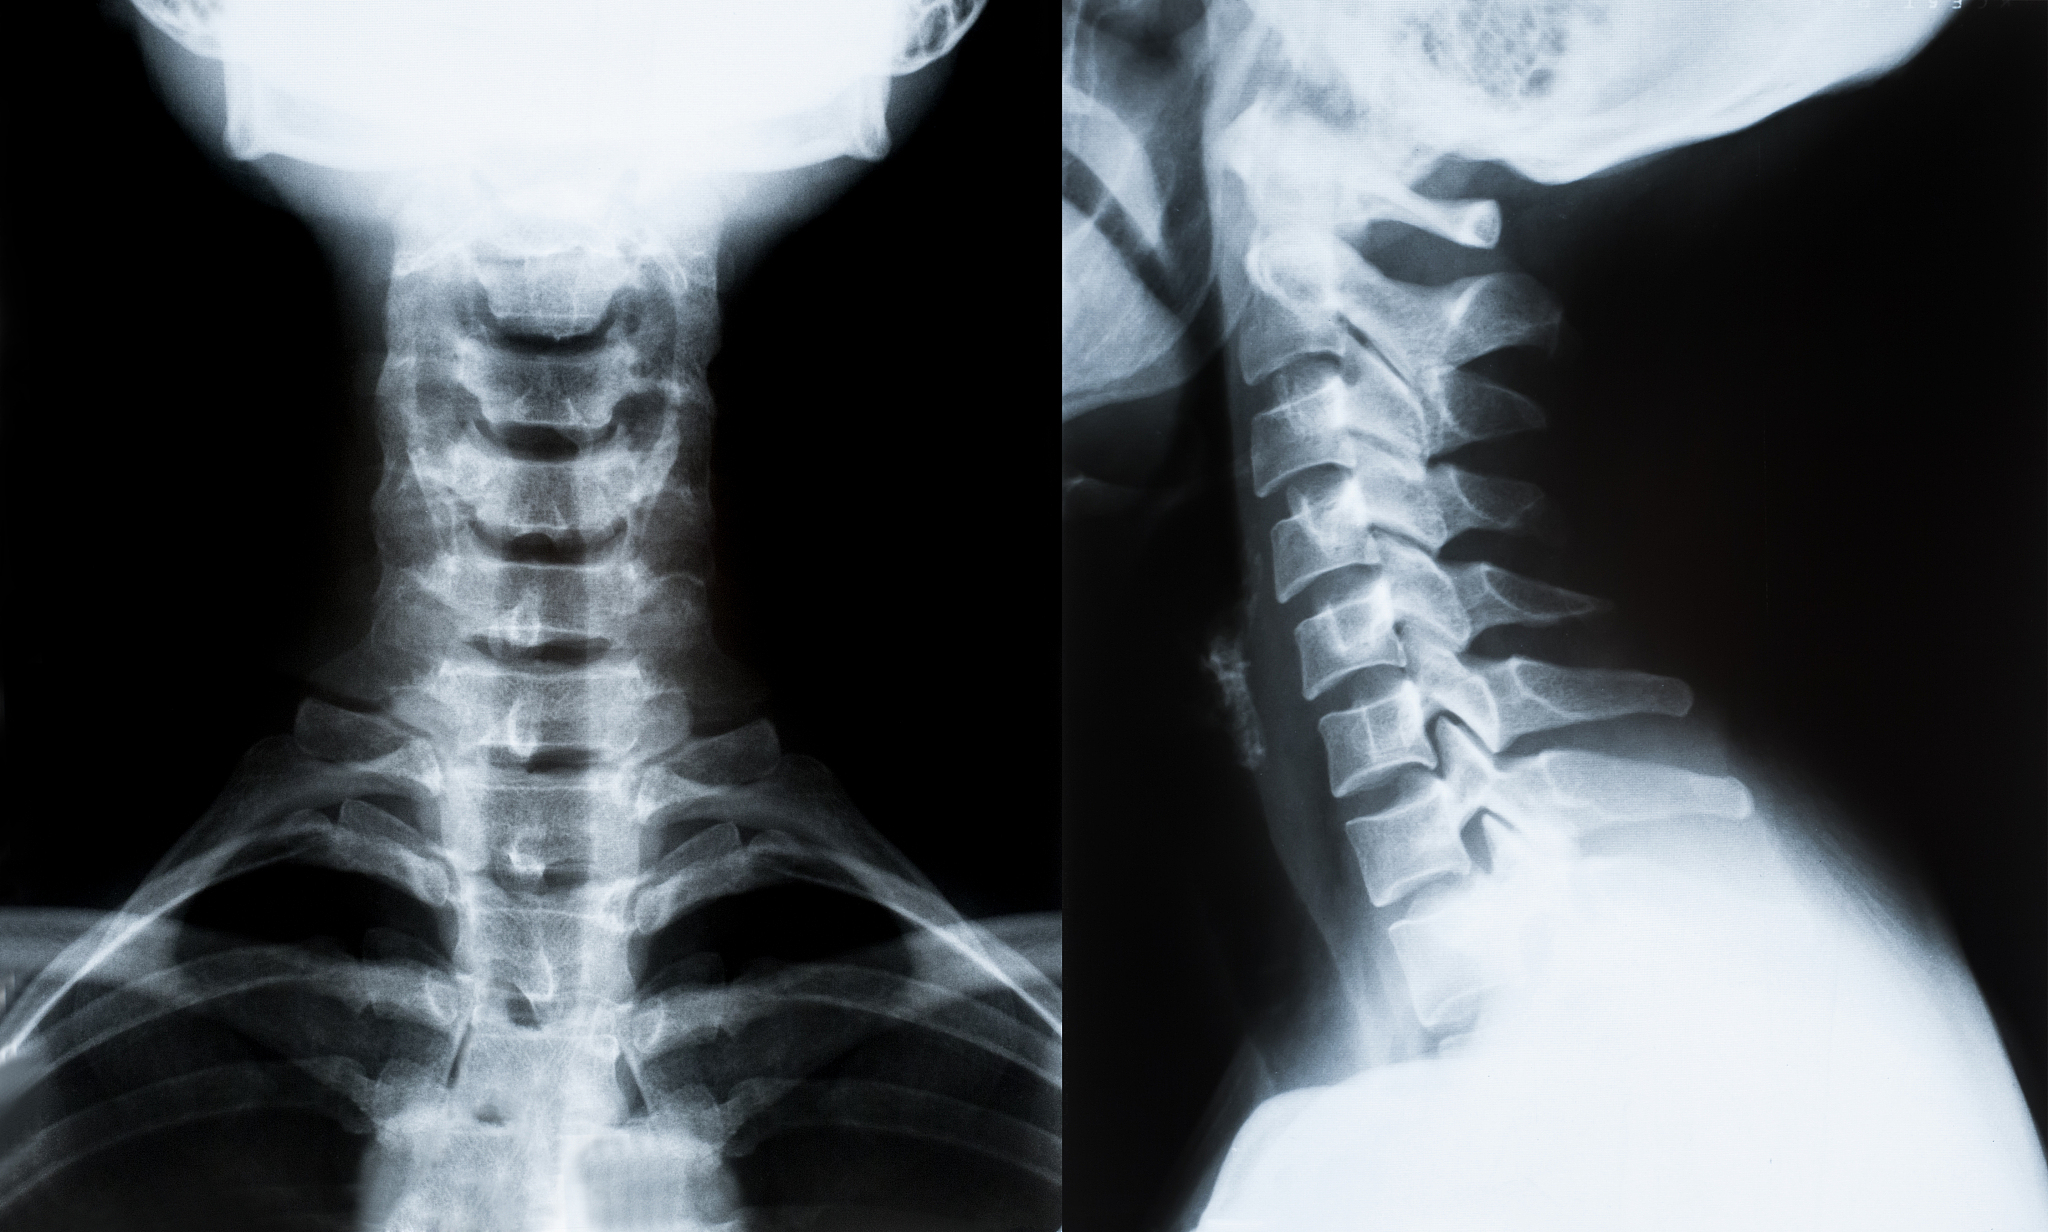

颈椎中央管扩张可以治愈吗

颈椎中央管扩张是一种病理性病变,通常可以通过手术治疗。手术可以通过减压来缓解症状和恢复神经功能。然而,手术并不能保证完全治愈,因为有些症状可能已经存在较长时间,有些神经损伤可能是永久性的。此外,手术风险也存在,如感染、出血和神经损伤等。因此,手术治疗是否适合需要根据个人情况来确定,应该与医生进行充分的讨论和决策。